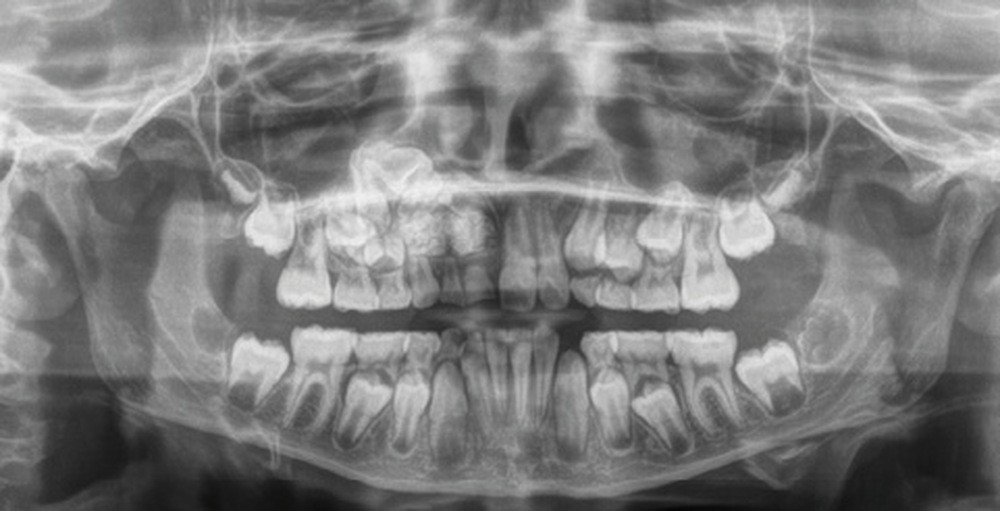

Les kystes et tumeurs bénignes osseuses maxillaires ou mandibulaires chez l’enfant sont le plus souvent asymptomatiques. Ces lésions osseuses sont découvertes de façon fortuite lors d’un bilan radiographique de routine réalisé par l’odontologiste pédiatrique ou l’orthodontiste [1-3]. Néanmoins, des lésions peuvent parfois se développer rapidement et être destructrices [1, 2]. Certains signes cliniques spécifiques à la chronologie de l’éruption dentaire chez l’enfant doivent nous alerter tels qu’un retard d’éruption dentaire ou une éruption dentaire asymétrique (fig. 1). D’autres manifestations cliniques, moins spécifiques à l’enfant, peuvent également orienter le clinicien sur la présence d’une pathologie osseuse sous-jacente : mobilité dentaire, douleur, tuméfaction, limitation de l’ouverture buccale, trouble neurosensoriel, etc. [3]. C’est la radiographie panoramique qui va ensuite mettre en évidence/confirmer la présence d’une lésion intra-osseuse (fig. 2).

La radiographie panoramique permet une première interprétation de la lésion osseuse (localisation, nombre, taille approximative, etc.). Cet examen est souvent complété par un bilan d’imagerie en trois dimensions de type Cone Beam [4]. Il précisera le volume et les limites de la lésion ainsi que ses rapports avec les structures anatomiques avoisinantes (tableau 1). Ces données radiologiques confrontées à l’examen clinique et à la fréquence relative des lésions permettent de réaliser un diagnostic d’intuition qui orientera la prise en charge.